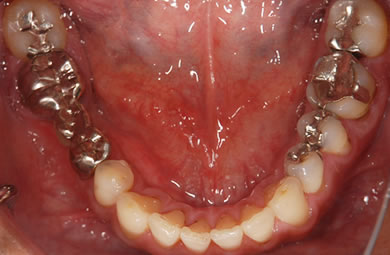

| 性別/年齢 | 男性 / 40歳 | ||||||||||||||||||||||||||||||||

| 主訴 | 虫歯を治療し、銀歯を含めた歯を白くしたい。 | ||||||||||||||||||||||||||||||||

| 治療方針 | 審美的・機能的回復をセラミック治療にて行う。 | ||||||||||||||||||||||||||||||||

| 治療内容 | メタルボンドセラミック4本(メタルボンドセラミック用の土台4本)、ハイブリッドセラミック6本(ハイブリッドセラミック用の土台1本) | ||||||||||||||||||||||||||||||||

| 総治療費 | 887,067円 | ||||||||||||||||||||||||||||||||

| 治療期間 | 7ヶ月 |